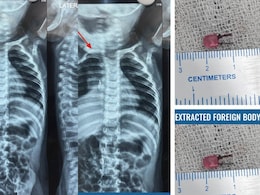

LED Bulb Found In 1-Year-Old Gujarat Boy's Windpipe After Weeks Of Illness

After weeks of failed treatments, it was discovered that what had been misdiagnosed as a common respiratory infection was actually a small LED bulb lodged deep within his windpipe.